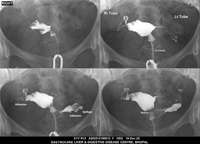

Section: HSG

Total: 49 Cases